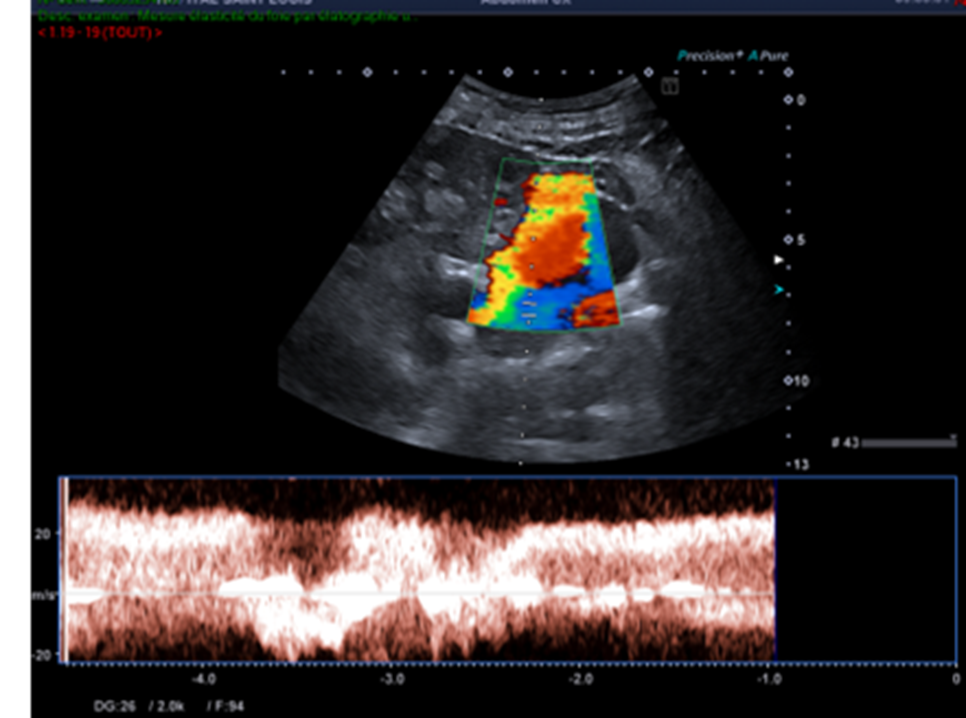

Voici le résumé des balayages et réglages réalisés par le manipulateur en échographie.

Ces nouvelles coupes (faisant apparaitre la rate, le doppler couleur et le doppler pulsé), montrent alors non pas un kyste rénal mais des volumineuses veines péri spléniques correspondant à des voies de dérivations spléno-rénales témoignant d’une hypertension portale probablement liée à la cirrhose sous-jacente.

Il est donc nécessaire de compléter son examen par une recherche d’autres signes d’hypertension portale notamment la présence d’ascite ou toute autre dérivation veineuse digestive (recanalisation de la VO, varices porto-portales, dilatation de la VMS et/ou dilatation des veines gastriques, varices mésentérique-caves (difficilement visibles en échographie-Doppler) ou la présence de varices porto-caves).